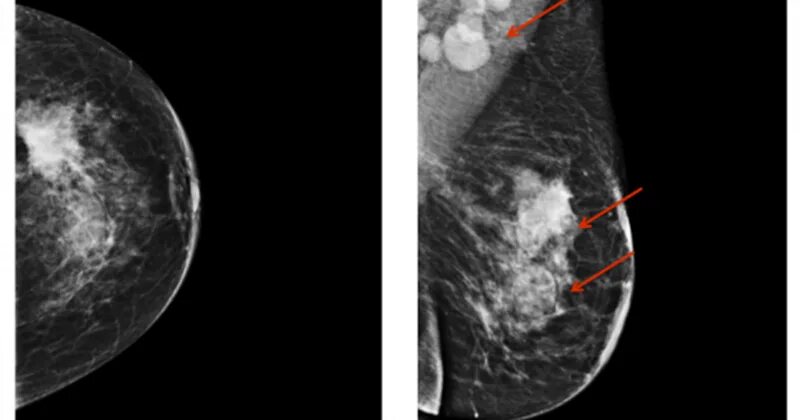

Диффузно фиброзно кистозные изменения